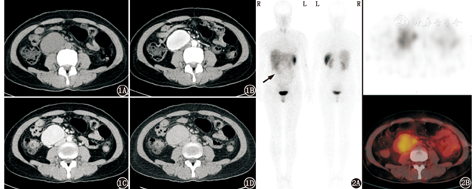

患者女,41岁,主诉腰部不适1个月,无发热、头痛、恶心、呕吐、腹痛、腹胀、腹泻、头晕、黑矇、大汗等症状。腹部CT发现右侧腹膜后软组织密度肿块;增强CT+三维重建图像示肿块大小约57 mm×40 mm,增强后明显强化,各期强化程度与血管相似,肿块局部与十二指肠分界欠清,下腔静脉呈受压性改变(图1)。实验室检查:24 h尿儿茶酚胺、血浆儿茶酚胺及其代谢产物(甲氧基肾上腺素、甲氧基去甲肾上腺素)、醛固酮(立位)、血管紧张素Ⅱ+肾素活性(立位)、神经元特异性烯醇化酶均正常。因临床拟鉴别副神经节瘤而行99Tcm-联肼尼克酰胺-酪氨酸3-奥曲肽(hydrazinonicotinamide-Tyr3-octreotide, HYNIC-TOC)生长抑素受体显像,平面显像可见右肾下方摄取轻度增高区,前位图像显示较清晰;SPECT/CT示病变位于下腔静脉前方,摄取轻度增高,与肝脏摄取程度接近(图2)。